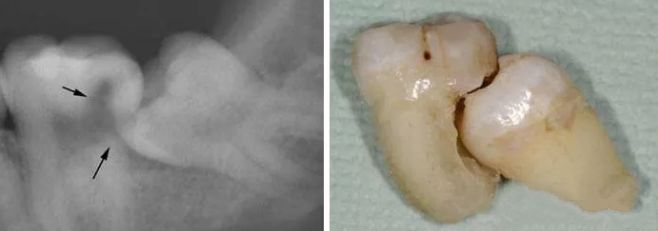

· 智齿所处的位置不同,其形态、结构也各有差异,一些患者的智齿结构极为复杂,拔除的难度十分之高,消耗的药品也有所增加,同时也十分考验医生的技术水平,在这种情况下,拔智齿的总费用就会更高一些。

▲阻生智齿